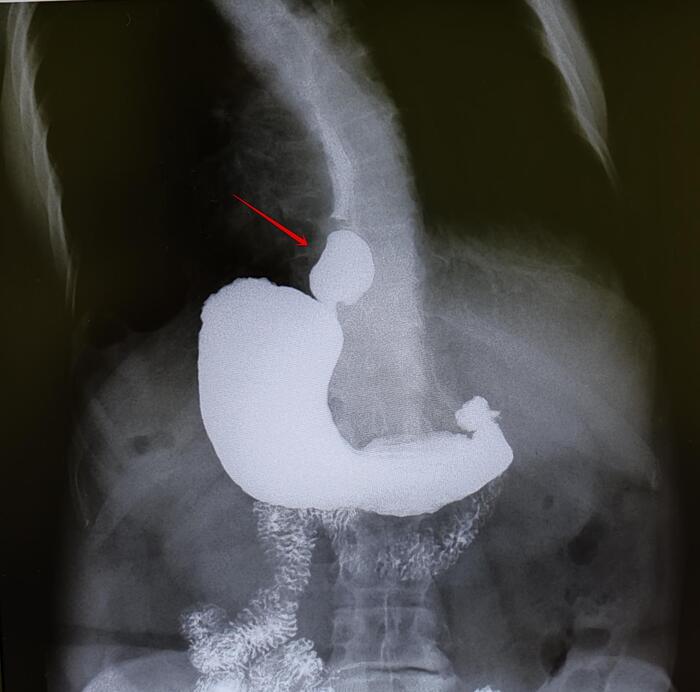

Варианты эностозов на КТ И МРТ.

Эностоз лечения не требует, динамическое наблюдение за его размером, ростом/его отсутствием.

Категория годности с диагнозом эностоз-по ст.10(Доброкачественные новообразования (кроме доброкачественных новообразований нервной системы и мозговых оболочек), новообразования in situ:),в) при наличии объективных данных без нарушения функции- А2-годен к военной службе.